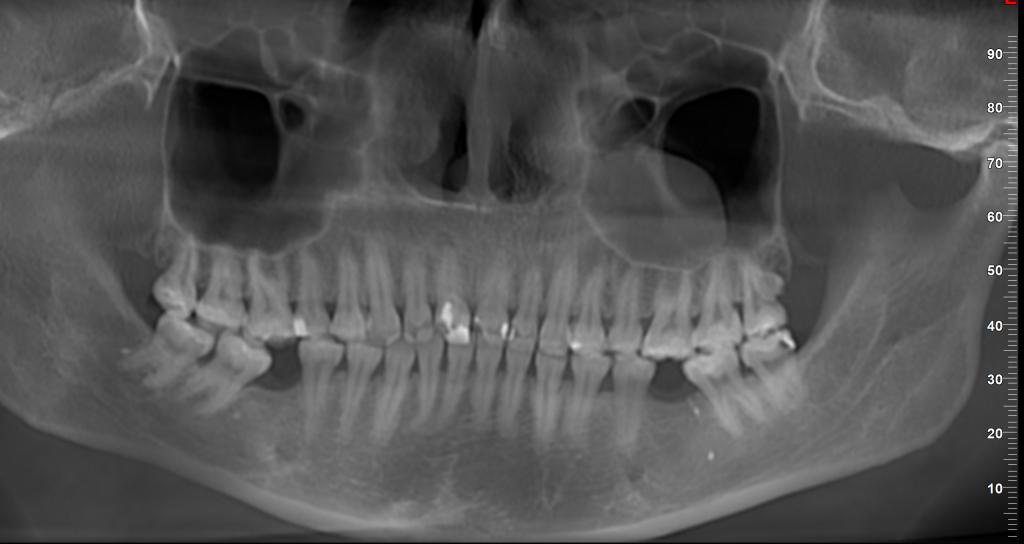

Добрый день. Уважаемые специалисты, что можете сказать по такой картине?

Вы обладательница 9(29) зуба! Красивые гайморовы - роскошные, воздушные )), Периодонтит 11 зуба, и возможно кариес в 38. Так и хочется вас посадить в своё кресло